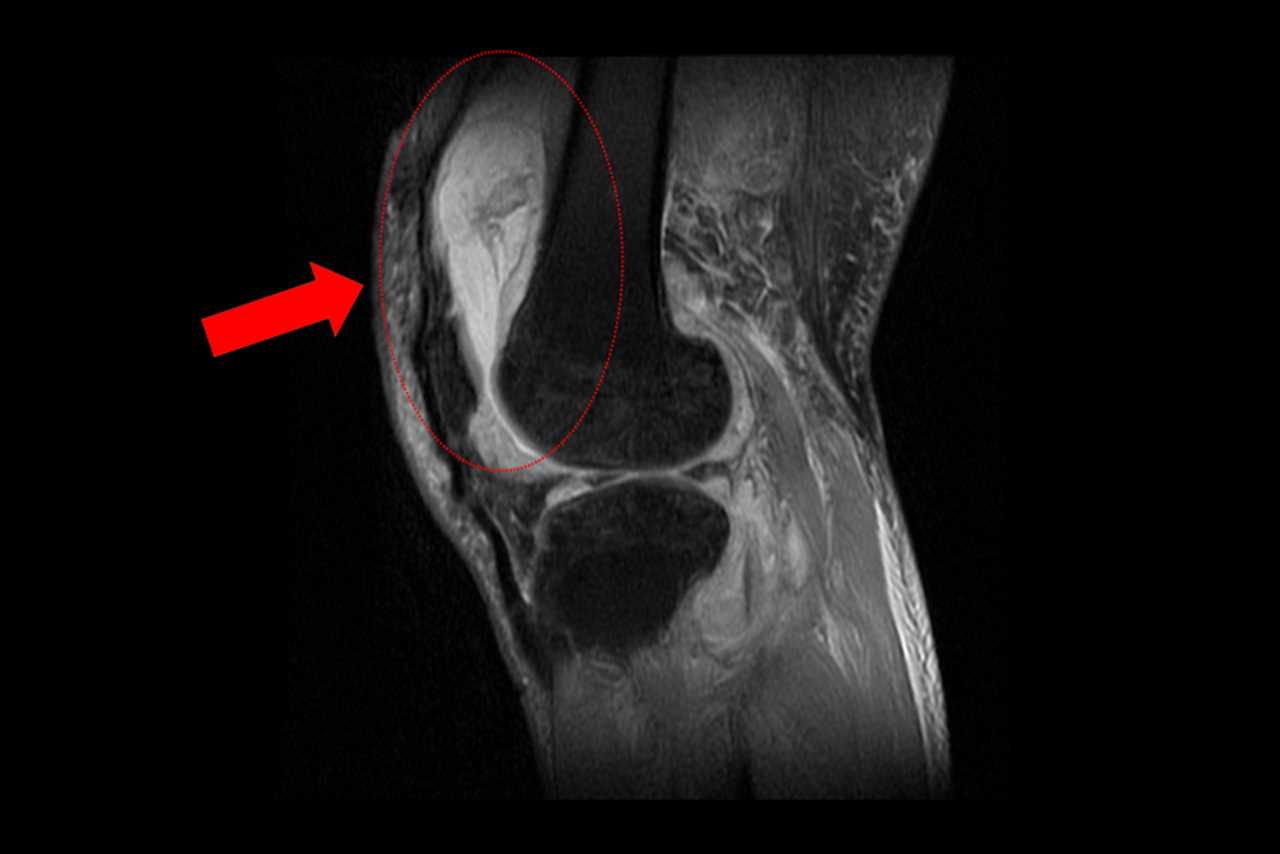

賴先生長期左膝腫痛、幾乎無法行走,就診時表示以為只是退化性關節炎,服用止痛藥、抽關節積水、熱敷復健數月卻越來越嚴重,來院時膝蓋已腫脹無法彎曲。關節中心主任周立展抽取膝關節液化驗後發現,白血球數值雖偏高,但並非典型的細菌感染,懷疑有其他原因。周主任安排病人住院,進一步X光與磁振造影檢查,顯示膝蓋內已有大量積液並化膿,屬於嚴重關節感染。

周立展主任避免病人感染惡化,緊急施行微創關節鏡清創手術,檢體送病理化驗後竟發現結核分枝桿菌,顯示並非單純膝蓋退化。周主任會診感染科與胸腔科醫師共同診斷,在病人痰液培養出結核菌,證實為「肺結核合併肺外感染」。結核菌最初在肺部引起感染,再經由血液或淋巴傳播,最後侵犯膝關節。病人住院期間接受抗結核藥物治療,一周後膝蓋腫脹消退,可正常彎曲行走;出院後仍須持續服藥至少九個月,並定期門診追蹤,確保結核菌完全清除。